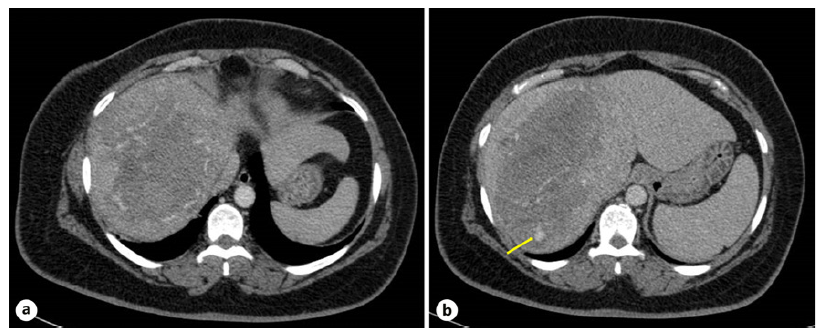

Prompt resuscitation with intravenous fluids and red blood cell units was initiated. Laboratory tests revealed a normocytic normochromic anemia with platelet count and coagulation profile within normal range and a cholestatic liver in jury (shown in Table1). Urgent abdominal CT angiography revealed 10 × 21 × 20 cm tumor of uncertain etiology in the right liver lobe with intratumoral active bleeding, with no signs of chronic liver disease (shown in Fig. 1).

Fig. 1 Abdominal contrast-enhanced CT. a A 10 × 21 × 20 cm tumor of uncertain etiology in the right liver lobe with intratumoral spontaneously hyperdense foci suggestive of blood products. b Active bleeding (arrow) in the early arterial phase in segment VII.